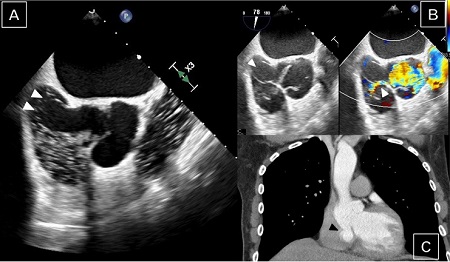

A 57-year-old male patient was referred to our hospital for catheter-based ablation due to paroxysmal atrial fibrillation. The patient reported intermittent palpitations, dizziness, and a reduced quality of life. Otherwise, the patient was healthy and had no previously diagnosed connective tissue disorder. During the preprocedural diagnostic work-up, a TEE was performed and revealed an ascending aortic aneurysm of 43 mm and a concomitant sinus of Valsalva aneurysm of 20 × 20 mm protruding into the right atrium (Figure 1A) associated with an aorto-right atrial shunt (Figure 1B). Right atrial dimensions were significantly enlarged. Mild aortic valve regurgitation was present and left ventricular systolic function was preserved. Subsequent cardiac CT scan confirmed the diagnosis of perforated sinus of Valsalva aneurysm with contrast medium shunting into the right atrium (Figure 1C). Intraoperatively, ruptured sinus of Valsalva aneurysm originating from the non-coronary and the right coronary sinus was present (Figure 2A). Native tricuspid aortic valve was highly asymmetric and right coronary cusp showed geometric height of only 15 mm in combination with a reduced effective height of 4 mm. (Figure 2A). The geometric height of the non- and the left coronary cusp was 22 mm and 18 mm, respectively. Despite this complex asymmetric anatomy, a valve-sparing procedure was planned, taking into account a good quality of the native cusps. First, the aorto-right atrial shunt was closed, and the right atrial roof restored using a bovine pericardial patch (40 × 20 mm) (Figure 2B). Next, aortic sinus tissue was completely resected preserving only both coronary buttons. During the reimplantation, the three aortic valve commissures were asymmetrically attached into the 28-mm GelweaveTM Valsalva Graft to mimic the original valve orientation and to achieve sufficient coaptation of aortic cusps. In addition, central plication suture of the right coronary cusp was performed to reach the effective cusp height of 8 mm. Furthermore, pulmonary vein isolation was performed with bipolar radiofrequency and the left atrial appendage was closed using an AtriClip® LAA Exclusion System. After weaning from cardiopulmonary bypass, the TEE showed a normal aortic valve function with only trace residual aortic regurgitation, no residual left-to-right cardiac shunt, and complete closure of the left atrial appendage. The patient recovered uneventfully after the surgery and was discharged in stable sinus rhythm and only trace aortic regurgitation with a mean transvalvular gradient of 13 mmHg.